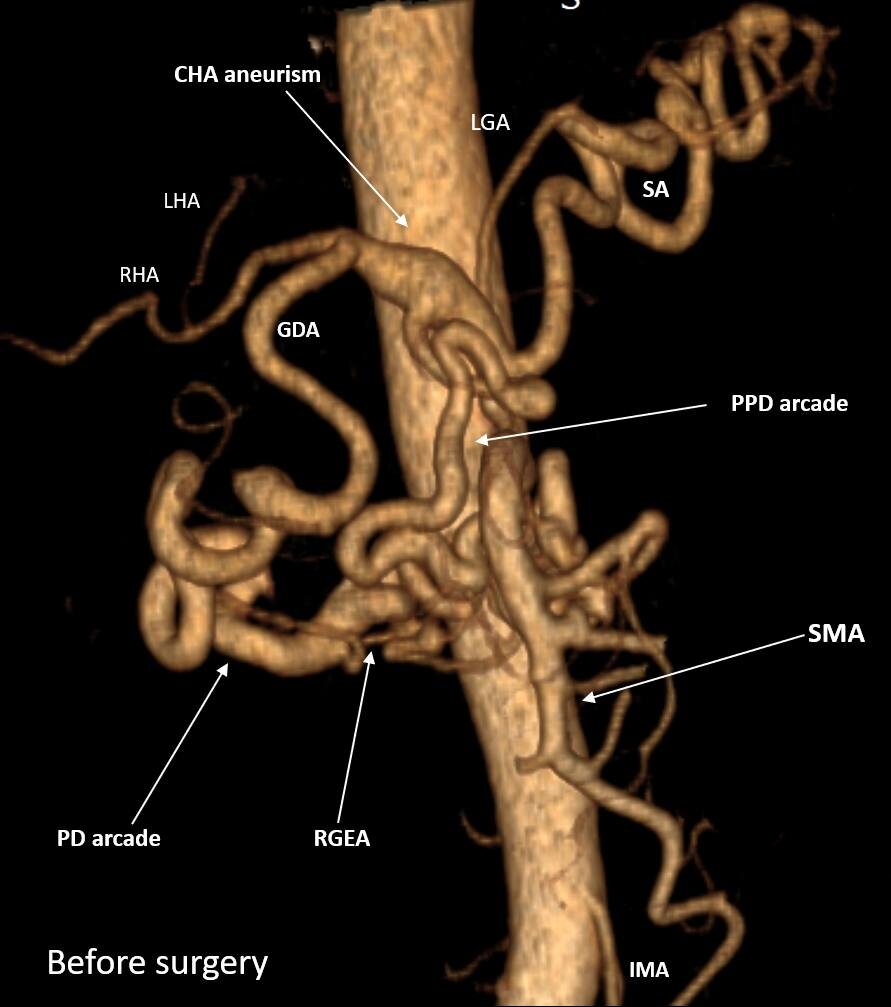

Панкреатодуоденальная резекция (ПДР) с транспозицией чревного ствола (ЧС) в правую общую подвздошную артерию и резекцией c протезированием общей печеночной артерии (ОПА) по поводу местнораспространенной протоковой аденокарциномы головки поджелудочной железы (ПЖ) с вовлечением гастродуоденальной артерии (ГДА) на фоне нестентируемого стеноза ЧС и аневризмы ОПА. Панкреатодуоденальная аркада (ПДА) и ГДА в данном случае  – основной источник кровоснабжения печени, желудка, 12-перстной кишки, поджелудочной железы и селезенки.

R0-PANCRETODUODENECTOMY ASSOCIATED WITH CELIAC TRUNK (CT) TRANSPOSITION INTO THE RIGHT COMMON ILIAC ARTERY AND COMMON HEPATIC ARTERY (CHA) RESECTION AND PROSTHETICS FOR LOCALLY ADVANCED PANCREATIC CANCER on the background of non-stentable long-lasting СT stenosis and CHA aneurism. Gastroduodenal artery (GDA) and pancreaicodudenal arcade in this case were the main sources of blood supply for the liver, pancreas, spleen, stomach and duodenum. ypT4N0 (48/0) M0

Месяц назад мы выписали домой пациента после вышеуказанной операции. У крепкого, 60-летнего мужчины за несколько месяцев до этого был обнаружен рак головки ПЖ. Важной особенностью было то, что также был выявлен протяженный и выраженный стеноз (сужение) чревного ствола (ЧС), одной из двух крупных артерий, снабжающих практически все органы брюшной полости. Это сужение было обусловлено (видимо, с рождения) давлением дугообразной связки диафрагмы на ЧС сразу после его отхождения от аорты. О том, что это сдавление было очень длительным, говорило то, что коллатеральные артерии (дополнительные сосуды, неработающие в норме и поэтому имеющие малый диаметр), которые обычно не видны на КТ, достигли диаметра, равного нормальному диаметру основных висцеральных артерий – ЧС и верхней брыжеечной артерии (ВБА). В нашем случае ЧС был представлен тонюсеньким сосудом, а коллатерали шли от ВБА и снабжали артериальной кровью печень, желудок, 12-перстную кишку, поджелудочную железу и селезенку. Коллатерали проходили через головку поджелудочной железы, опухоль которой вросла в эти сосуды, от которых зависело кровоснабжение жизненно важных органов (см. фото), и за счет этого опухоль перешла из разряда резектабельных в разряд местнораспространенных. Мало того, длительные нарушения гемодинамики привели к образованию аневризмы (патологического расширения) общей печеночной артерии (ОПА) – ключевого сосуда, через который снабжались в нашем случае не только печень, но и остальные ранее перечисленные органы.